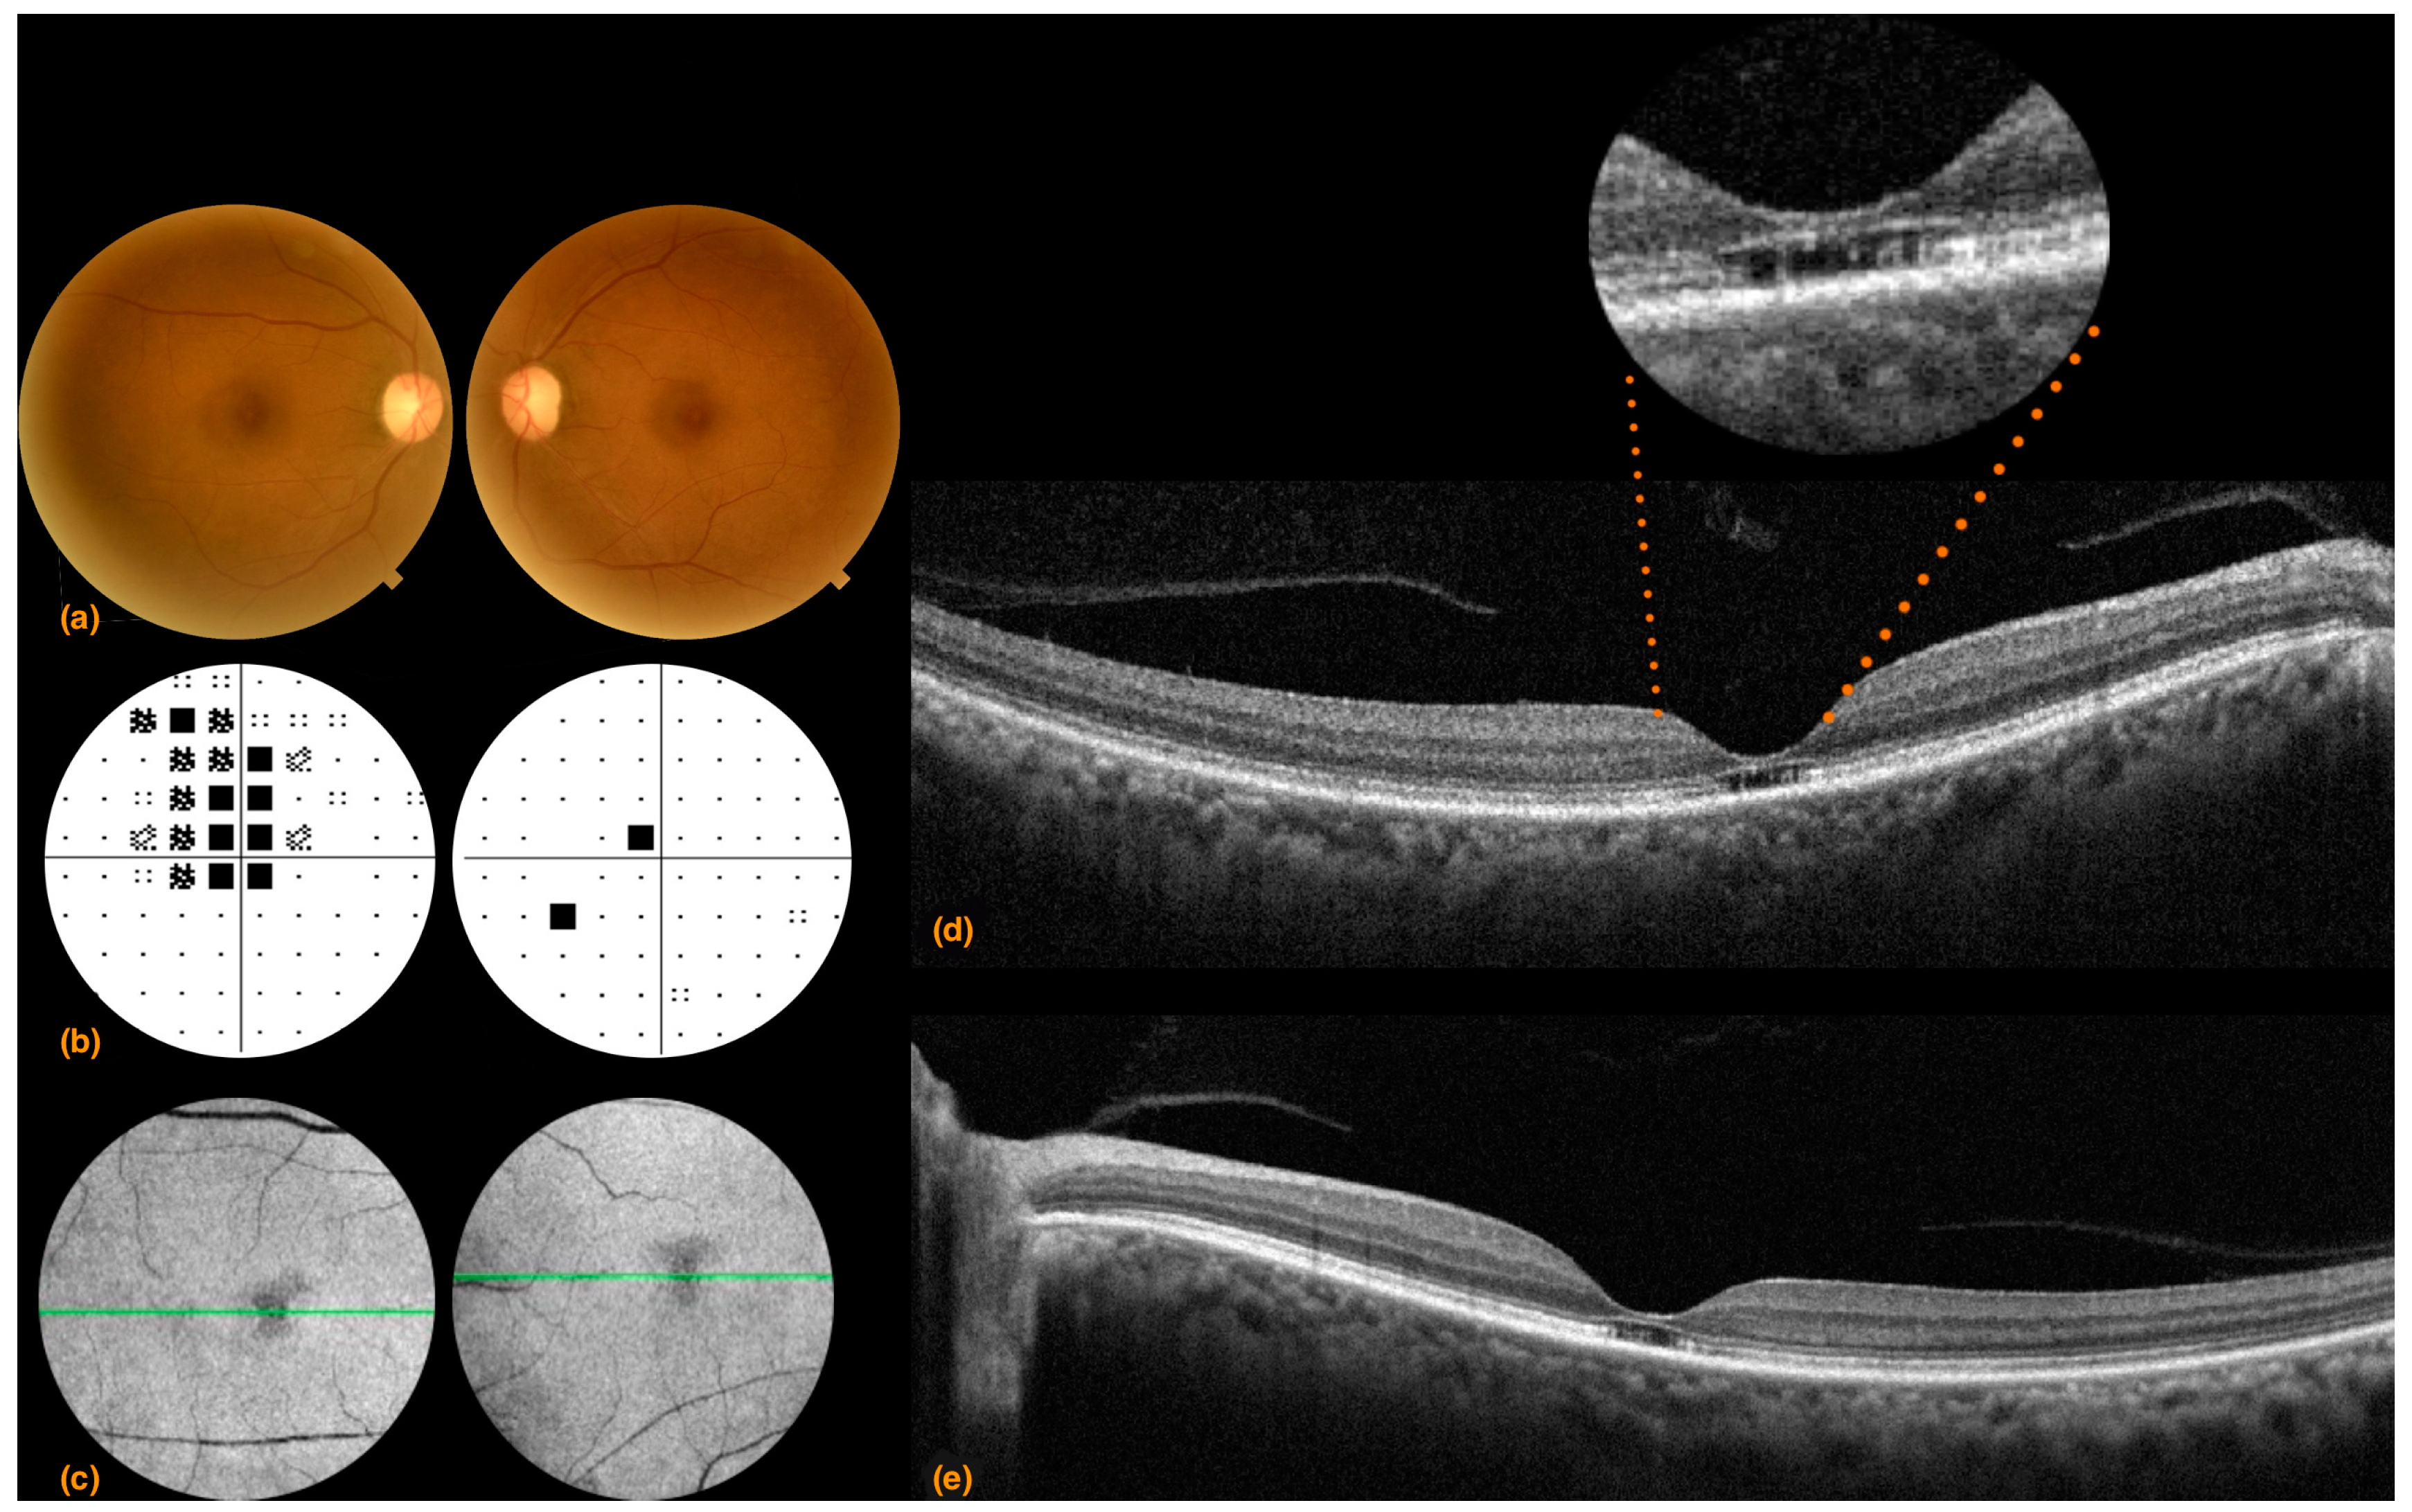

3.1. Case 1